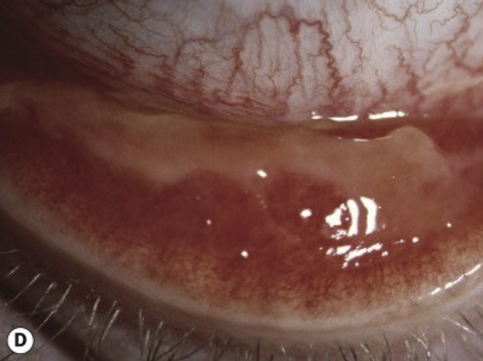

What conjunctival changes occur in cicatricial trachoma?

Conjunctival scarring

• Mild infection: linear or stellate scarring

• Severe infection: broad confluent scared (Arlt lines)

• Superior tarsal effected more then other areas of conjunctiva

<p>Conjunctival scarring </p><ul><li><p>Mild infection: linear or stellate scarring</p></li><li><p>Severe infection: broad confluent scared (Arlt lines)&nbsp;</p></li><li><p>Superior tarsal effected more then other areas of conjunctiva&nbsp;</p></li></ul><p></p>